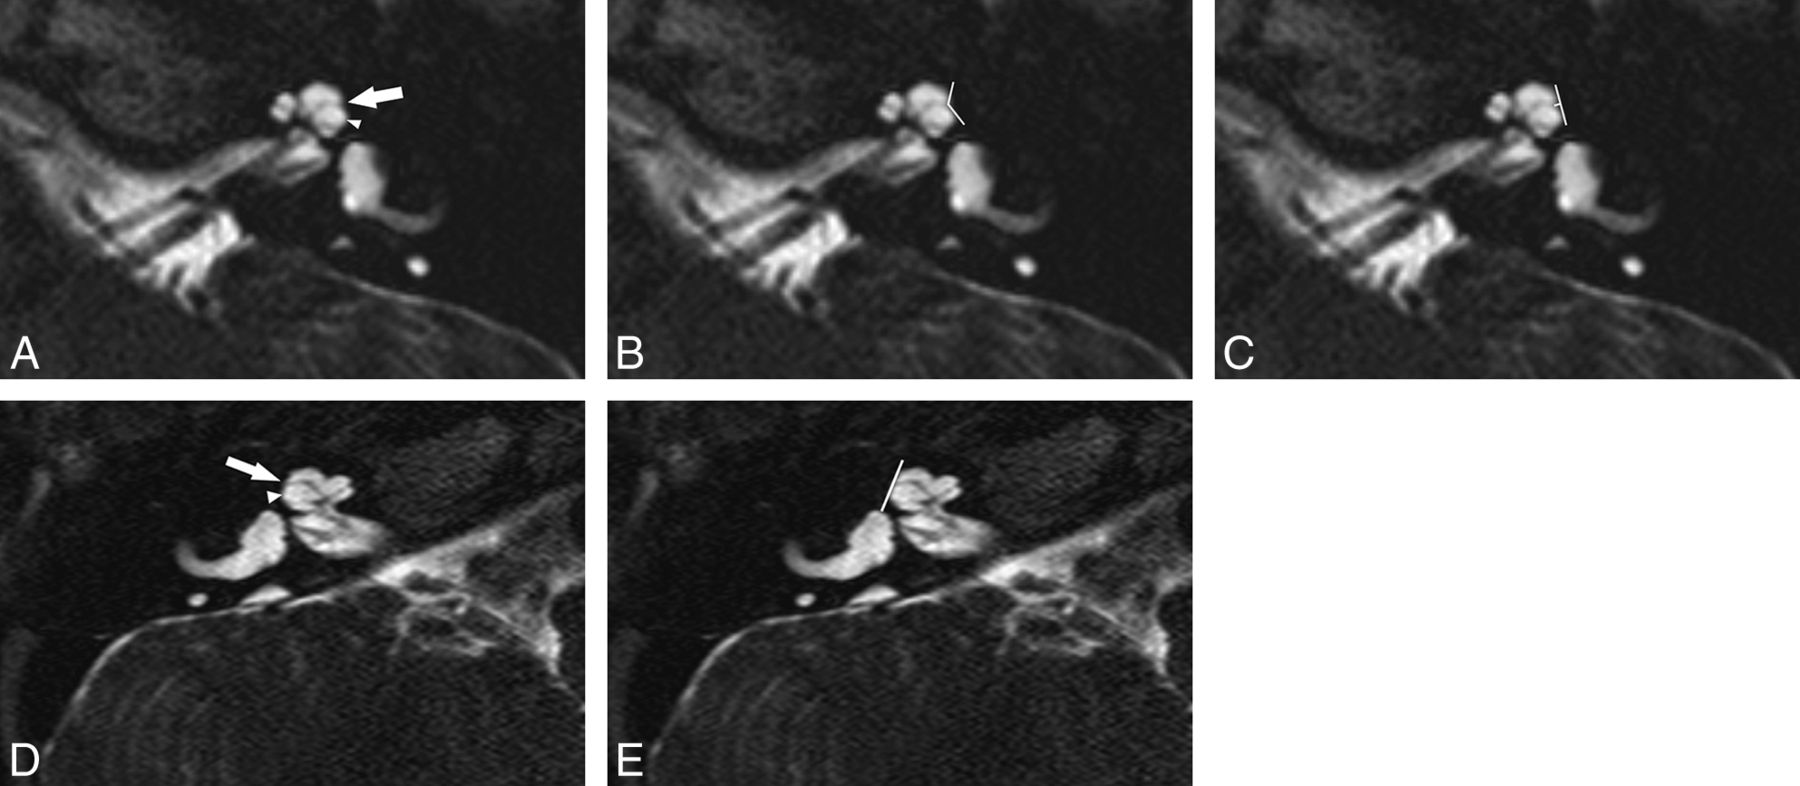

Axial 3D T2-weighted image through the cochlea in a normal-hearing ear. A, A normal lateral notch is demonstrated (arrow). B and C, At the same level, angle and depth measurements are demonstrated using electronic calipers (lines). The angle was measured as 84° with a depth of 0.6 mm.

Abnormal R2 notch in 2 different IP-II malformation ears, both with profound SNHL. A–C, A shallow obtuse notch is present (arrow). The scala vestibuli is enlarged (arrowheads) with anterior bowing and high insertion of the second part of the interscalar septum. The measured angle at the same level is 132° (B) with a depth of 0.3 mm (C). D and E, In the other patient, no lateral notch is seen (arrow) and the scala vestibuli is enlarged (arrowhead). At the same level, the angle is 180° and the depth is 0 mm (E).

The 94 normal ears had a mean R2 angle of 80.9° ± 11.4° (range, 57°–132°) and a depth of 0.54 ± 0.14 mm (range, 0.3–0.9 mm). The 98th percentile angle was 101° with a depth of 0.31 mm (Fig 2). There was no significant difference in any measurement with age (P = .8) or sex (P = .37). Morphologic analysis of the membranous labyrinth demonstrated a normal cochlea in all normal ears with normal hearing. The second portion of the interscalar septum was seen in 34 ears (36%). Cochlear nerves were present in all ears. Five ears (5%) showed a diminutive bony island separating the lateral semicircular canal from the vestibule. No patient had a dilated endolymphatic duct.